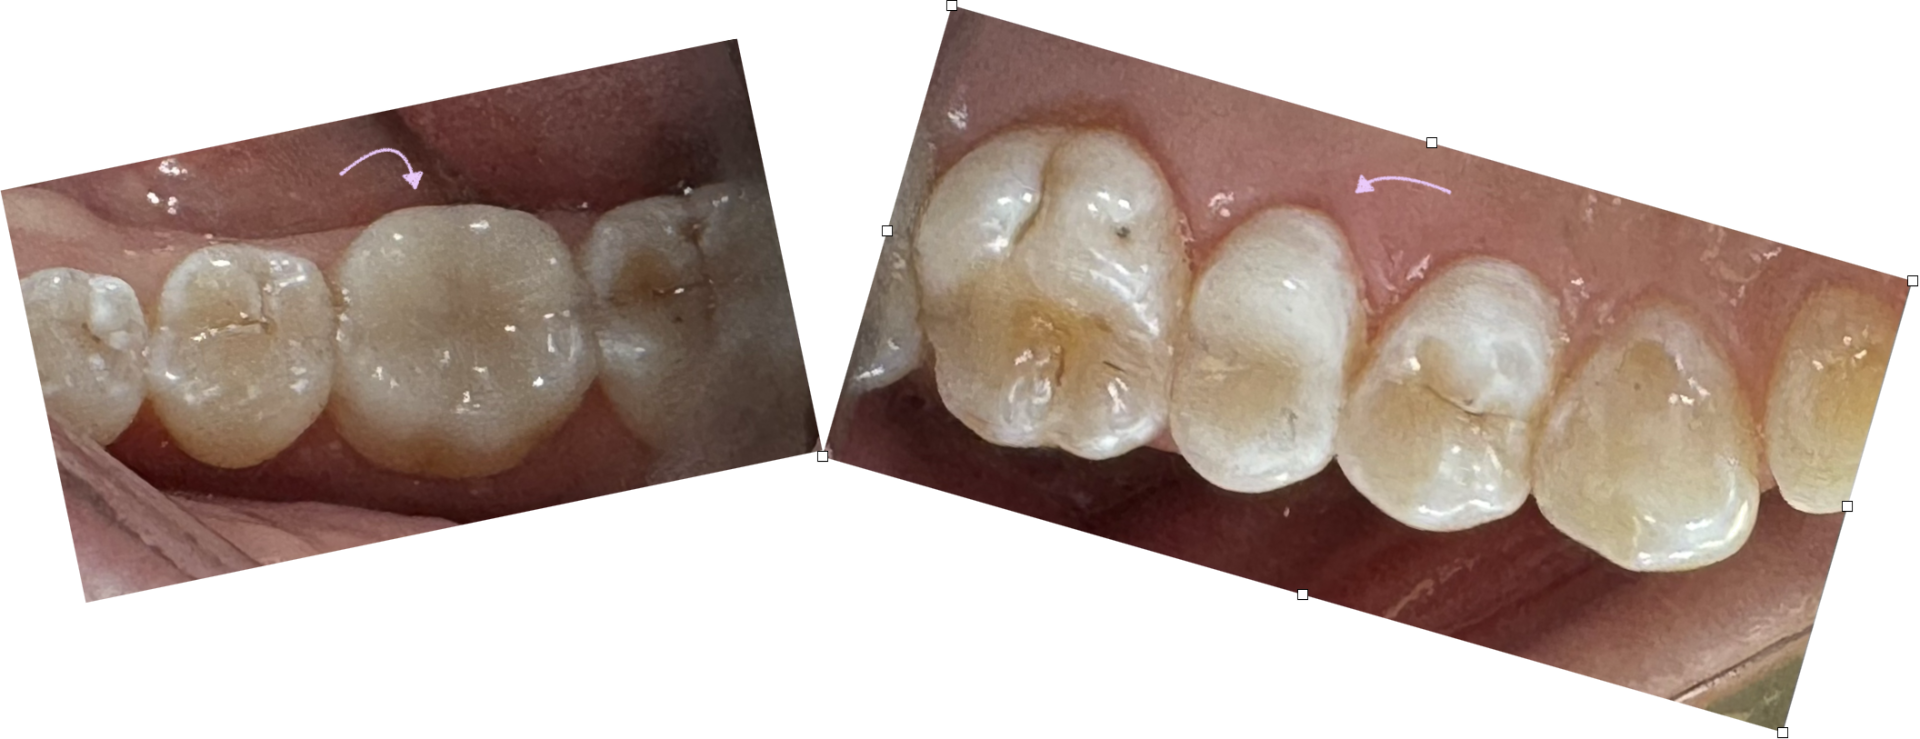

Der blev lagt en behandlingsplan for at bevare tandsættet. Den flækkede tand blev erstattet med et implantat. Samtidig fik patienten fem keramiske hætter på de tænder, der havde dybe revner, og til sidst en bidskinne til at passe på tænderne om natten.

De tre revnede tænder i overkæben blev givet en skånsom beslibning. Der blev foretaget en 3D-scanning af tænderne og fremstillet tynde keramiske hætter hos Moderne Dansk Digitalt Lab i Viby i Aarhus ved hjælp af computerstyret design og fræse-robotter.

Billederne viser en 3D-printet model, hvor man kan se de tænder, der er blevet beslebet, og de færdige keramiske hætter. Den grønne pil peger på den flækkede tand.

Her er det færdige resultat med restaureringerne monteret i munden. Keramikken er limet meget fast til tanden, så der sker en integration af keramik og tand. Det giver en meget stærk restaurering, selvom den er tynd. Restaureringerne er slidstærke og holder deres form i mange år.

Æstetisk er der også en meget fin integration af keramik og tand.